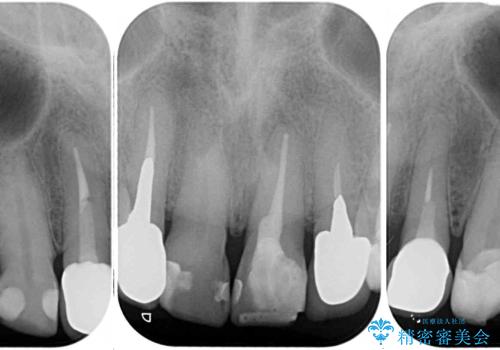

- コンポジットレジンやクラウンなど、様々な医院で治療を受けたために、統一感がなくなってしまった前歯を綺麗にしたいとのことで来院された患者様です。

当初は前歯6歯をオールセラミッククラウンで補綴する予定でしたが、前歯が綺麗に仕上がったことで、奥歯まで延長して補綴することとしました。

黄ばんだ前歯や白すぎたクラウン、プラスチックの継ぎ接ぎなどを全てオールセラミッククラウンの統一感のある前歯に仕上げました。